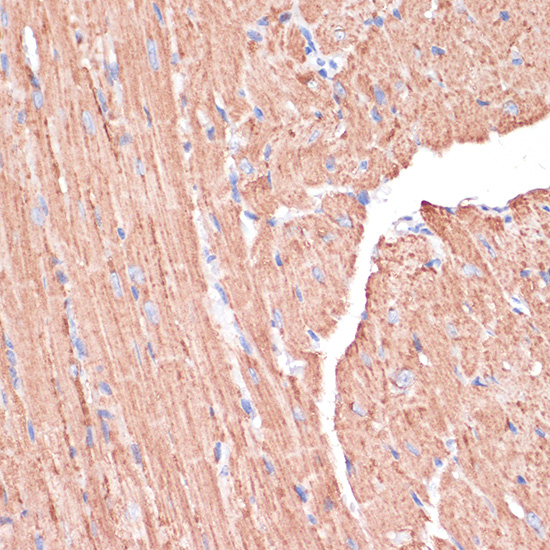

Immunohistochemistry of paraffin-embedded Mouse heart using PGD antibody.